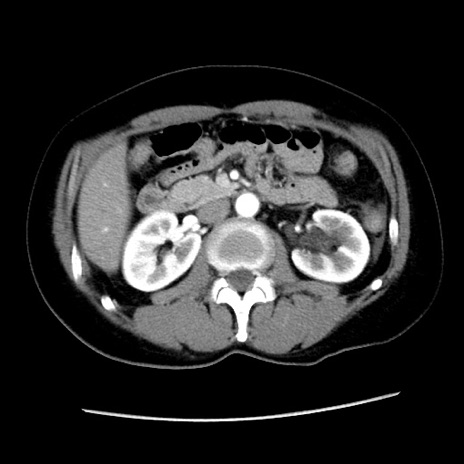

症例10(横断像)

【症例】 50歳代女性

【主訴】 腹痛

【現病歴】前日生レバーを食べた。今朝に排便あり。 昼前に突然発症の腹痛を生じ、当院救急外来を受診した。

【身体所見】 意識清明、腹部:平坦、軟、下腹部やや左を中心に圧痛・反跳痛あり、筋性防御あり

【データ】WBC 7800、CRP 0.07